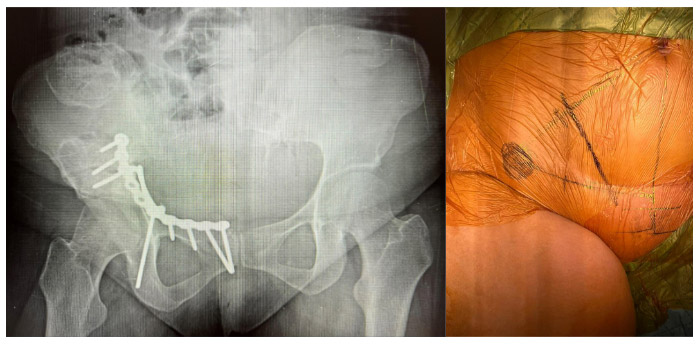

During and after surgery:The image shows the planning of the incision line (pararectus) and the fixation of the fracture with an anatomical titanium plate after placement.